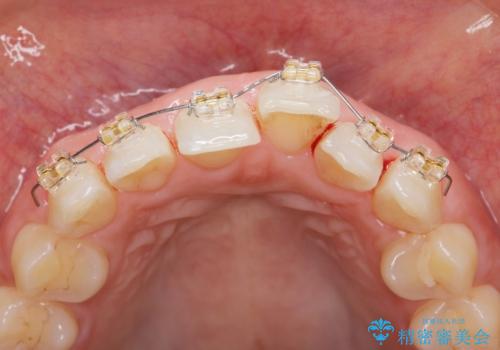

出っ歯に見える前歯の改善 部分ワイヤーとマウスピース矯正

- インビザライン +部分ワイヤー矯正

- 出っ歯に見える前歯の改善を希望され、来院されました。

マウスピースでは改善の難しい歯の動きを部分ワイヤー矯正で整えたのち、奥歯の噛み合わせや細かい歯の並びをマウスピース矯正インビザラインで整えていきます。